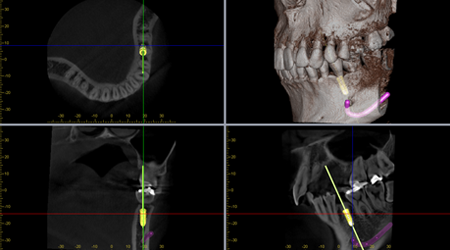

最新の精密機器を

使用した精密診療